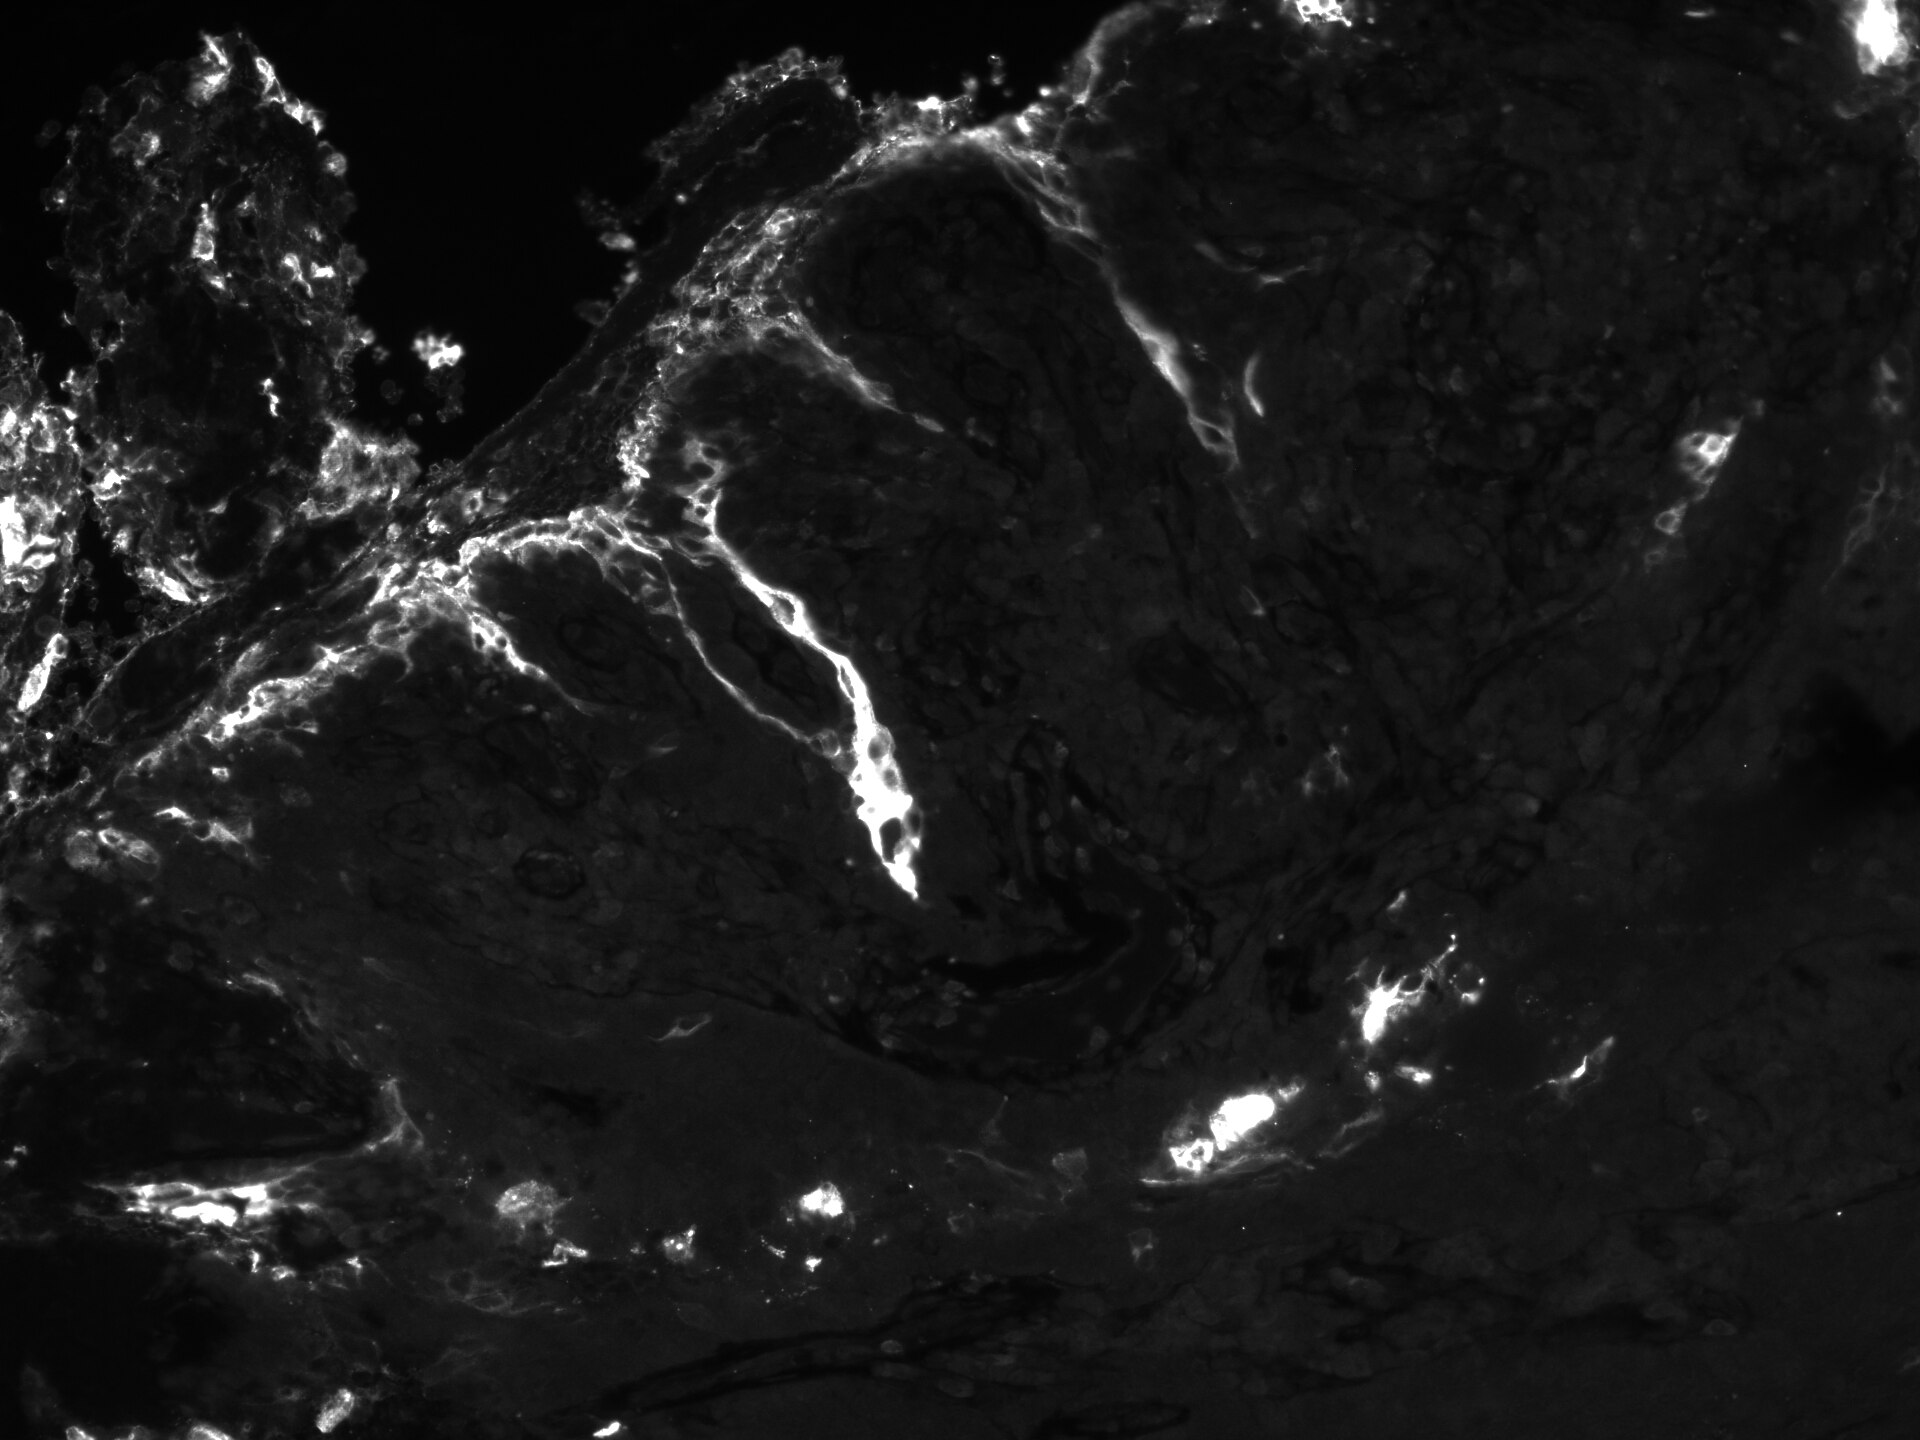

Immunohistochemistry-Paraffin: CEA Antibody (PARLAM 4) [NBP1-97718] - Human head and neck squamous cell carcinoma section. Antigen retrieval at pH 9. CEA antibody at 1:100. IHC-P image submitted by a verified customer ...read more

Immunohistochemistry-Paraffin CEA NBP1-97718

IHC-P Human 03/30/2020

ApplicationImmunohistochemistry-Paraffin

Sample TestedHead and neck squamous cell carcinoma

SpeciesHuman

CommentspH 9 antigen retrieval